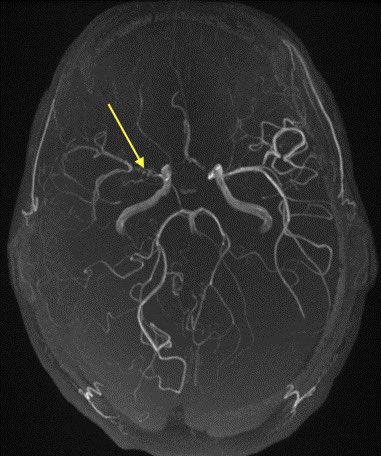

Imaging of Moyamoya disease/syndrome Imaging: Thread-like intracranial ICA/MCA with attenuated branches and “puff of smoke” appearance on DSA Co